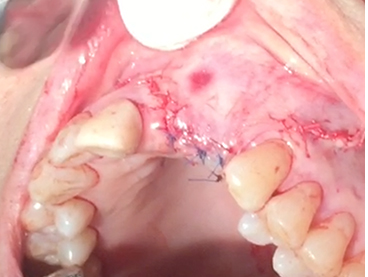

Partial edentulous clinical cases